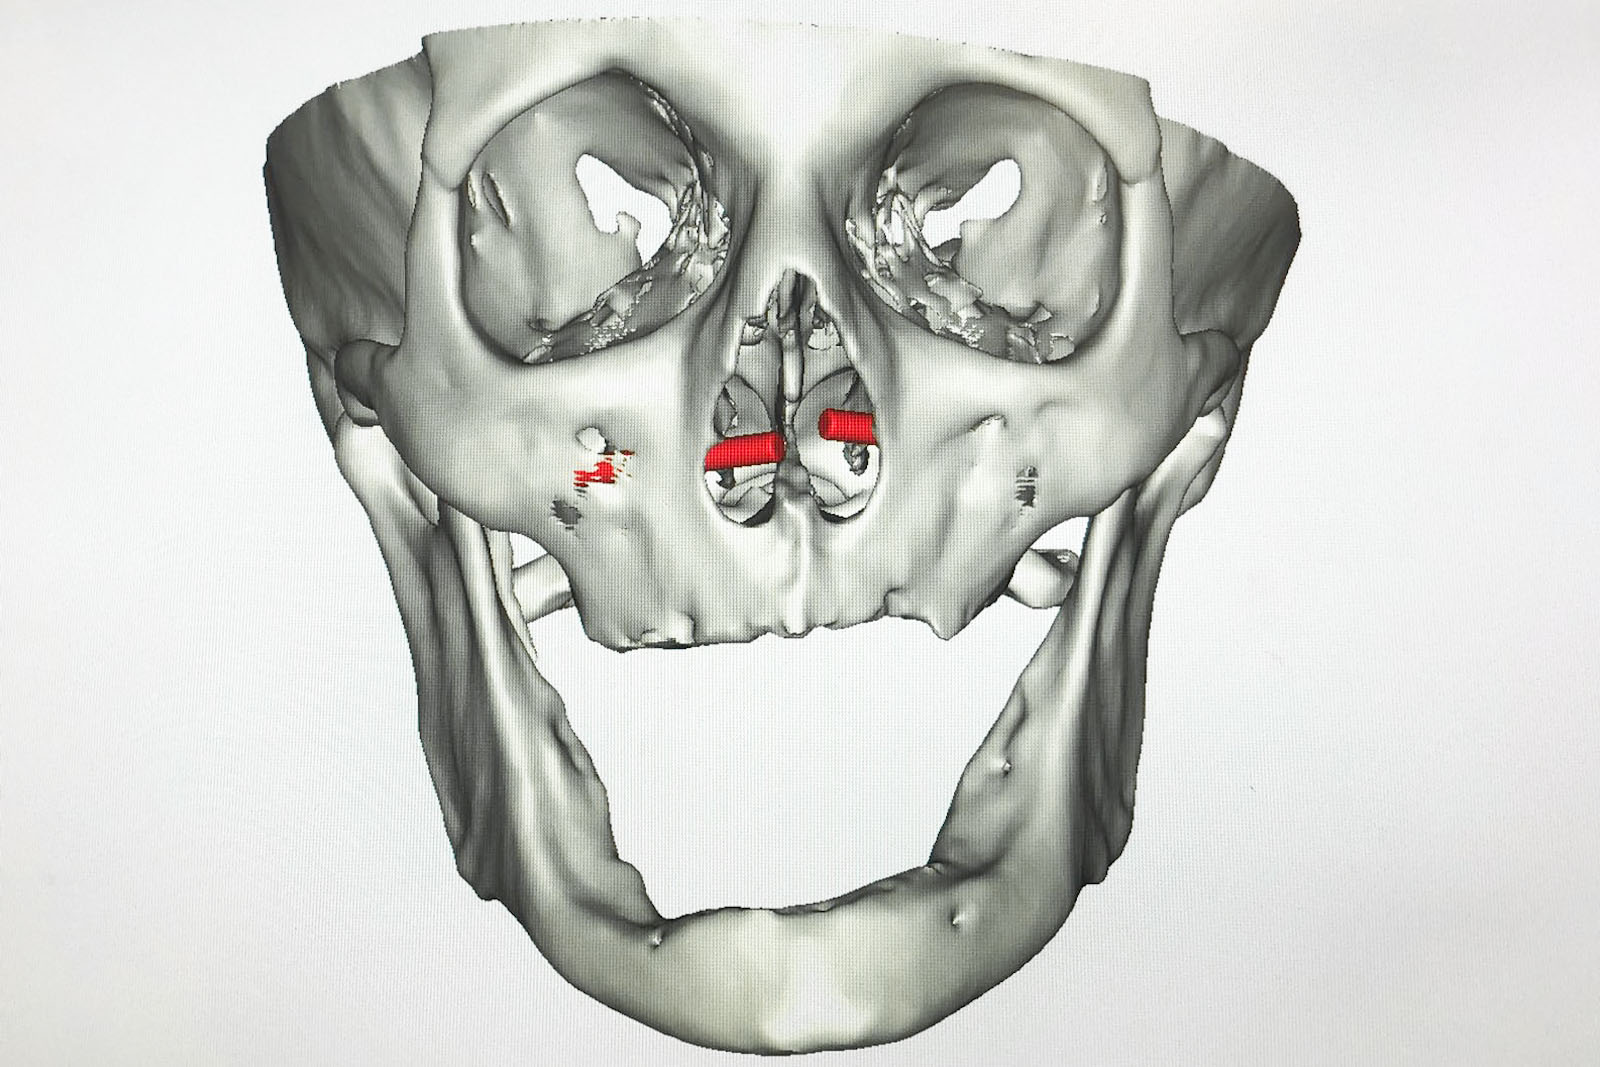

Chory po resekcji tkanek/narządów twarzoczaszki wymaga wnikliwej diagnostyki obrazującej zakres ubytku oraz stan podłoża kostnego. Wykonuje się zdjęcia radiologiczne RTG pantomograficzne szczęk OPG, konwencjonalną tomografię komputerową CT, stożkową tomografię komputerową CBCT, ukazującą trójwymiarowy obraz twarzoczaszki, oraz w razie potrzeby rezonans magnetyczny NMR. Możliwy jest również druk modeli 3D w skali 1:1 dowolnej części twarzoczaszki.

Diagnostyka ma za zadanie wykluczenie wznowy wyciętego nowotworu oraz pomoc w ocenie tkanki kostnej w okolicy ubytku. Ocena kości pozwala na zaplanowanie zabiegu wszczepienia implantów jako przyszłego fundamentu niezbędnego dla mocowania protez poresekcyjnych lub epitez twarzy.

Należy dokonać doboru odpowiedniego systemu i rodzaju implantów przydatnych do przyszłego umocowania protez poresekcyjnych. Systemy implantologiczne używane dla tych celów to:

- implanty czaszkowe – krótkie, zwykle o długości 3 mm i 4 mm, w formie śrub, które wszczepia się w kości pokrywy czaszki oraz twarzoczaszki w zależności od potrzeby oraz rodzaju braku tkankowego; system implantów czaszkowych oferuje komplementarne rozwiązania protetyczne typu belki Doldera, zaczepy i magnesy, które umożliwiają stabilne umocowanie protez zewnętrznych, np. ucha czy nosa

- implanty Zygoma – długie, 30–52,5 mm, przeznaczone do mocowania w strukturze kości jarzmowej; w przypadku istnienia ubytku poresekcyjnego szczęki mocuje się je w kikucie kości jarzmowej, która pozostaje po resekcji; implanty Zygoma umożliwiają stabilne umocowanie protez poresekcyjnych po wycięciu częściowym lub nawet całkowitym szczęk ze względu na swoją konstrukcję i wymiar. Pomocne bywają również przy mocowaniu epitez np. nosa (czytaj dalej...)

Zastosowanie współczesnych technik obrazowania trójwymiarowego umożliwia precyzyjne zaplanowanie pozycji implantów czaszkowych, tak by ektoprotezę stabilnie osadzić na podłożu.